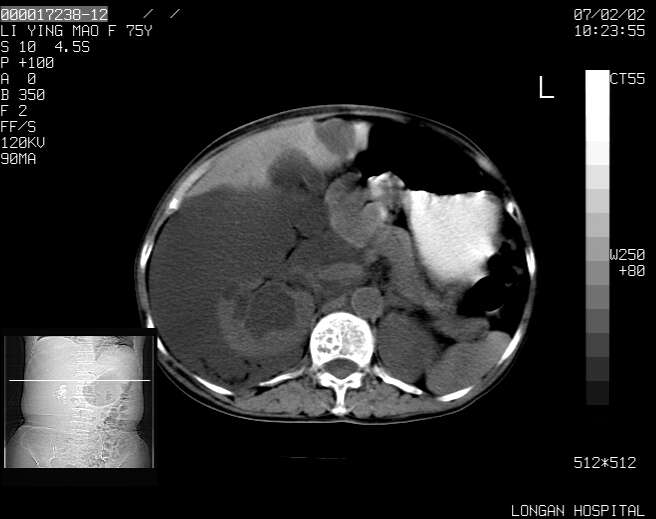

以下是引用dyqct在2007-2-10 8:53:00的发言:[br]考虑:1、肝脏多发囊肿[br] 2、左肾囊肿,右肾多发结石并积水。[br] 3、右胸少量积液。[br] 4、右肾周包裹性积液或淋巴管瘤(有见缝就钻的征象、薄隔、小结节状钙化)?[br] 5、腰椎动脉瘤样骨囊肿?[br] [br] [br]